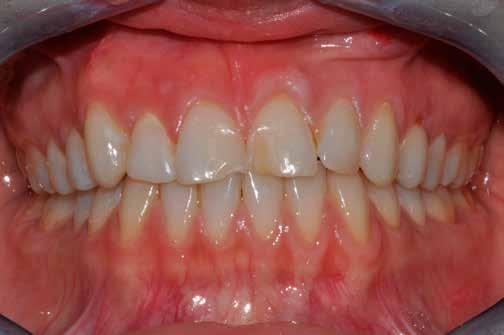

Egy 34 éves páciens esztétikai problémával érkezett. A természetesen keskeny metszőfogak miatt kisebb diasztémák és fekete háromszögek voltak láthatók a front régióban. A rések korábban kompozittal történő zárása már megtörtént, azonban az eredmény nem felelt meg az elvárásoknak (1. ábra). A fekete háromszögek továbbra is láthatóak voltak, és a kompozitanyag jól kivehetően helyezkedett el a fogak felszínén. A 11-es és 21-es fogak szélessége között aszimmetria mutatkozott, a korábbi restaurációk nehezen tisztíthatók voltak, és gyorsan elszíneződtek (2. ábra). A frontfogak palatinális felszínén retenciós drót volt rögzítve, a 11-es és 21-es fogak pedig kompozittal történő sínnel voltak összekötve (3. ábra). Bármilyen további kezelés során a retenciós drót eltávolítása szükséges, mivel az akadályozza a megfelelő approximális restaurációk kivitelezését. Az első konzultáció során teljes fotódokumentáció készült. Egy gyors kompozit mock-up segítségével bemutatásra kerültek a lehetséges esztétikai eredmények. A kezelési terv elfogadását követően időpont egyeztetésre került sor a beavatkozás elvégzésére.

1. ábra: A mosolyról készült fénykép a kezdeti vizsgálat során.

2. ábra: Közeli felvétel a felső metszőkről; A kompozit restaurációk jól láthatóak voltak.